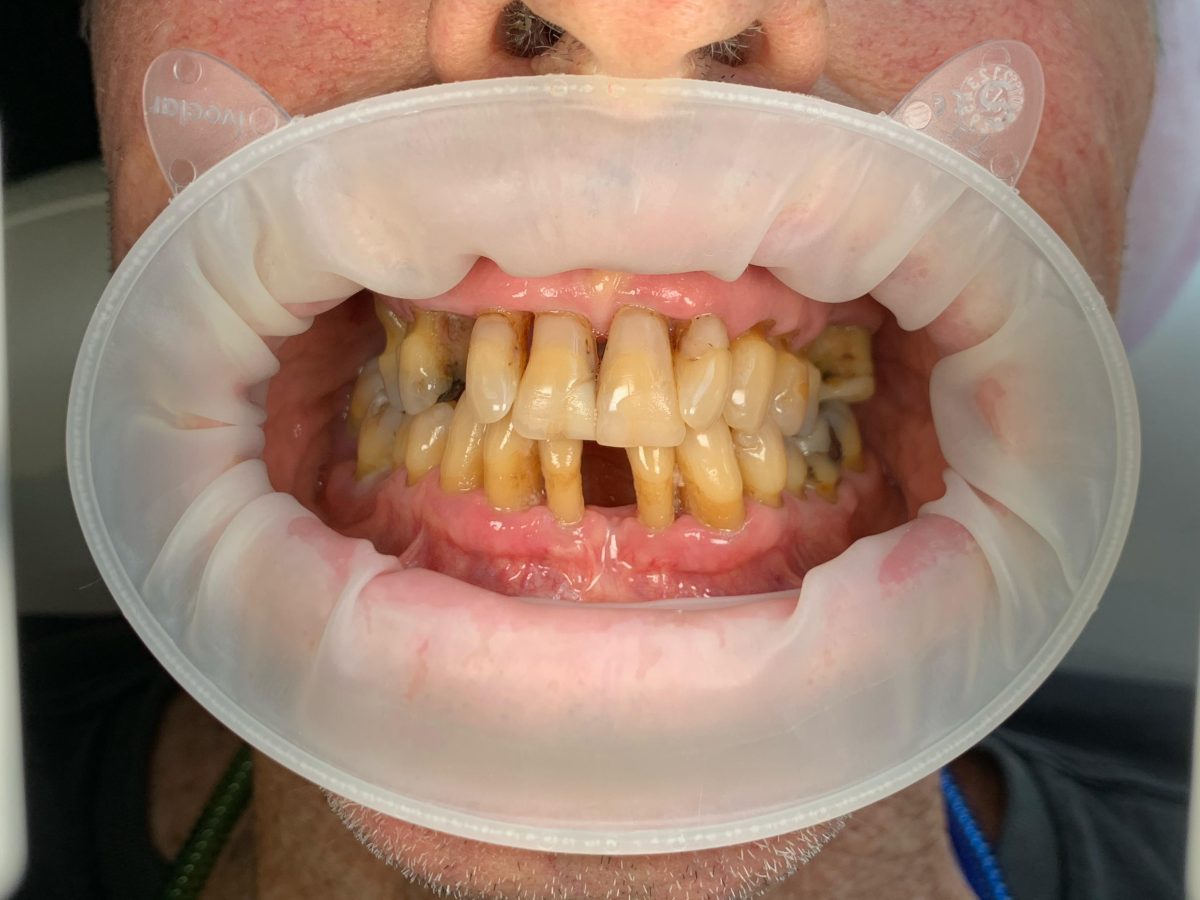

All-on-X dental implants are a full-arch restoration solution designed for patients with multiple missing, damaged, or failing teeth. The treatment uses four, five, or six dental implants to support a fixed full-arch prosthesis, restoring both function and aesthetics.

Full mouth rehabilitation is a comprehensive dental treatment designed to restore both function and aesthetics for patients with severely worn, damaged, missing, or failing teeth.

Treatment may include a combination of:

Each treatment plan is customized based on the patient’s oral condition and long-term goals.